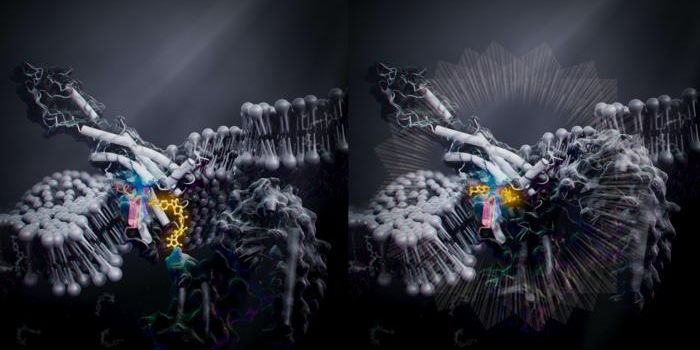

SEP 09, 2024Drug Discovery & DevelopmentThere’s No Turning Back Not long ago, solving the crystal structure of a protein required an entire PhD. Gro ...